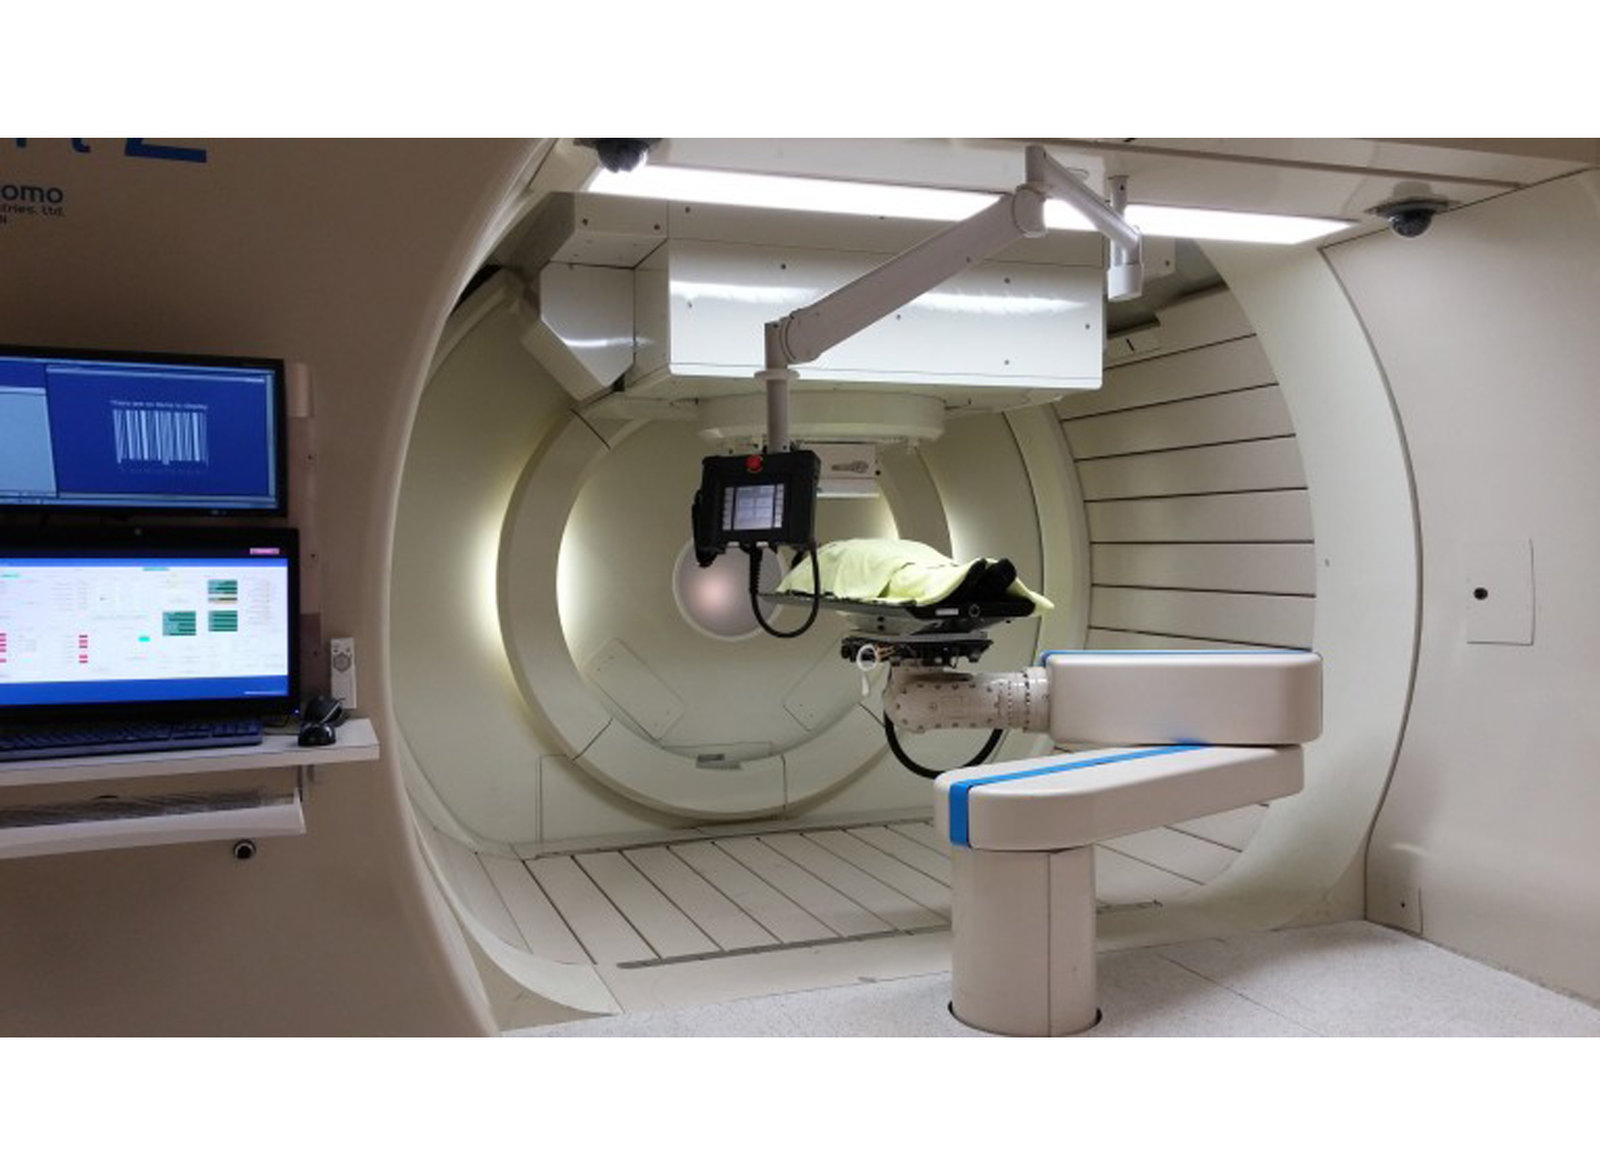

桃醫治癌新利器 6D亞瑟刀

2014-05-08 20:50:00近幾十年來,癌症一直位居國人十大死因的第一位,醫界治療癌症的技術也不斷提升,有桃園醫院引進新技術,希望縮短療程時間。